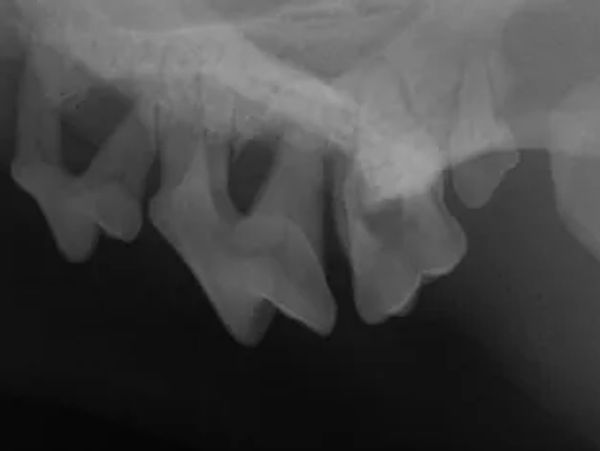

Submit dental radiograph sets for interpretation. You will receive a written report for your records.